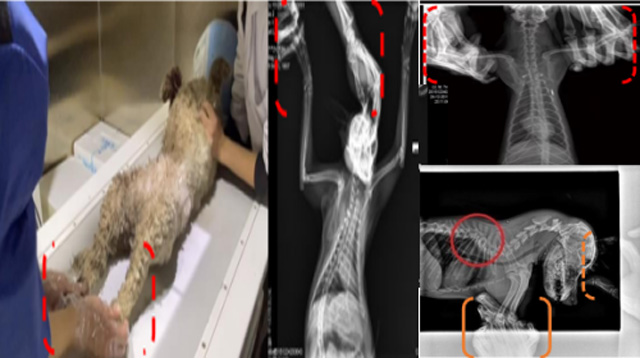

现在宠物医疗设备得到高速发展,现在有越来越多的宠物诊疗机构配置X射线装置如宠物DR。宠物骨折或者有其他疾病不能通过直观看出来的。宠物诊所医生都会使用宠物DR来做辅助检查。但是有时候宠物医生没有加强防护,就在宠物DR室给宠物拍X片做检查。这样也是会受到X射线的辐射。因为X射线上岗是属于职业病危害岗位。长期的辐射会对人体造成一定的危害。宠物医生也需要接受X射线照射的上岗前都必须进行放射工作人员的职业健康体检。体检不合格的话是不能担任放射工作的。未经上岗前职业健康体检的劳动者从事接触职业病危害作业的行为,已经违反了《中华人民共和国职业病防治法》第三十五条规定,依据《中华人民共和国职业病防治法》第七十五条规定,需要进行整改罚款??钩栉锓派湔锪苹疃谌粘9ぷ髦?,对本机构的X射线危害的职业病防治,需要知道并做到以下内容: